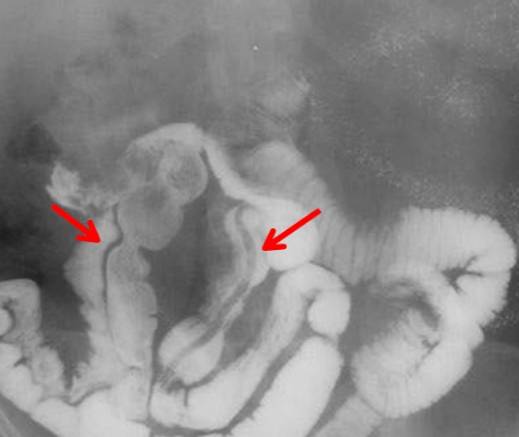

Дополнительными методами обследования являются: метод толстого мазка (метод Като); метод обогащения (метод осаждения Фюллеборна и флотационный метод Калантарян); перианально-ректальный соскоб; отпечаток на липкой ленте.

image

Так как вышеперечисленные методы обследования не позволяют уточнить, какой именно цепень паразитирует в организме человека: свиной или бычий, то необходимо тщательное изучение зрелых члеников. Так, боковые ответвления у матки бычьего цепня насчитываются в количестве от 18 до 32 штук. В то время как у матки свиного цепня боковых ответвлений с одной стороны будет от 8 до 12 штук.